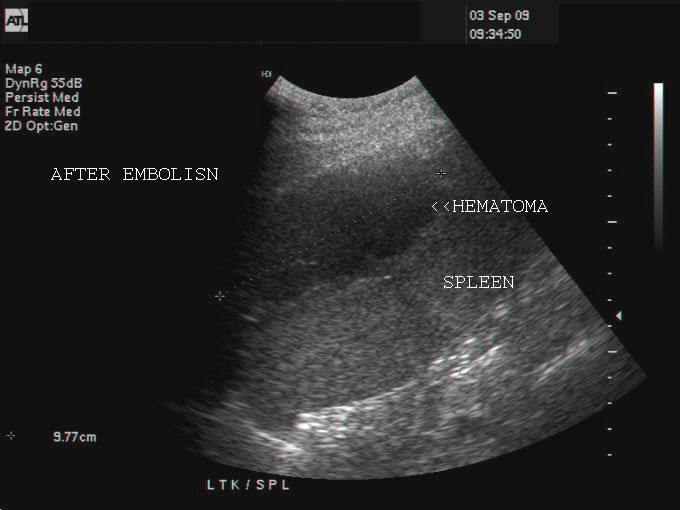

Ultrasound images showing reduction in size of hematoma after coil embolization

This patient had a rupture of spleen with large hematoma in the spleen. This is seen in the ultrasound images of the spleni hematoma (images on topmost row). The splenic hematoma measured almost 12 x 6 cms. Coil embolization of the splenic artery was done to control the bleeding.Sonography of the spleen shows (2nd row from top) after embolization shows reduction in the size of hematoma. CT scan (also called CAT scan) images of the splenic hematoma also show reduction in size of the hematoma. The coil is seen as a markedly hyperdense object in the splenic hilum (arrowhead- COIL EMB in CT images). There are 2 types of coils used for arterial embolization, the microcoils and macrocoils. All above images are courtesy of Shlomo Gobi, Israel.